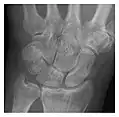

Triquetral fracture usually occurs on the dorsal aspect by impingement from the ulnar styloid or avulsion of strong ligamentous attachment. The dorsal avulsion fracture or "chip fracture" appears as a small bony fragment on the dorsal aspect of the triquetrum and is best detected on the lateral view(Figure 4). When radiography is negative in patients with high suspicion of a fracture, both MRI and MDCT will be of value. However, it has been shown that MRI is superior for detecting trabecular fractures in carpal bones.

a

b

Figure 4: Dorsal triquetral fracture of the left wrist in a 30-year-old man after a trauma. (a) Anteroposterior radiograph shows a normal appearance. (b) Lateral radiograph of the same wrist demonstrates a chip fracture off the dorsal aspect of the triquetrum (arrow).[1]